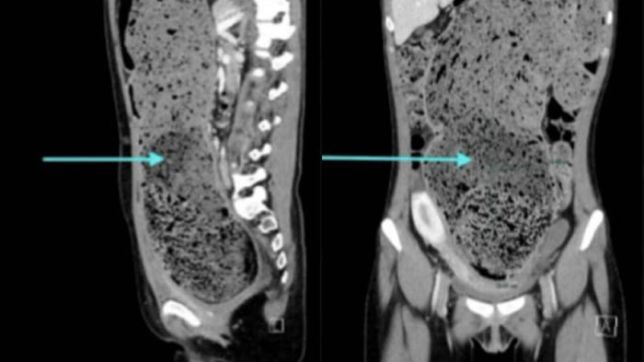

Uma tomografia computadorizada confirmou a gravidade do quadro ao mostrar que o intestino da jovem estava completamente obstruído por fezes acumuladas. A equipe médica também identificou um cólon sigmoide redundante, estrutura anatomicamente mais longa que o habitual, com 15 cm de diâmetro, o que favorece episódios persistentes de constipação.

Uma tomografia computadorizada revelou que o intestino da jovem de 25 anos estava completamente obstruído por fezes acumuladas